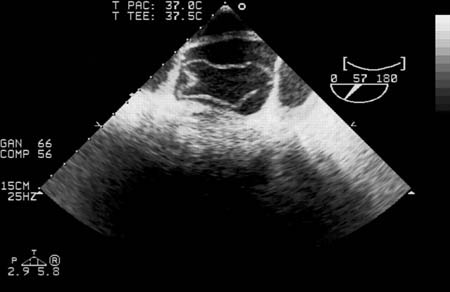

Transesophageal echocardiography (transverse aortic section) showing a circumferential dissection of the ascending aorta in a 30-year-old patient with features of Marfan syndrome

Bouzas-Mosquera A, Solla-Buceta M, Fojón-Polanco S. Circumferential aortic dissection. BMJ Case Reports 2009; doi:10.1136/bcr.2007.049908